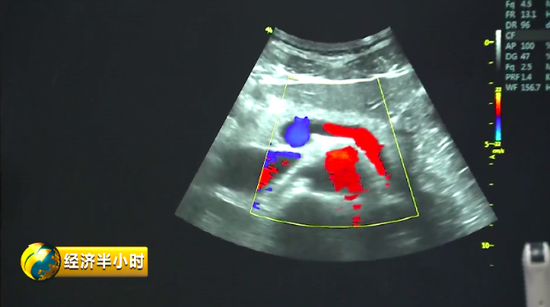

彩色B超有一个特殊的彩色B超设备,不仅能够精确诊断,还能帮助大夫有效地给予患者治疗。也就是说,在治疗疾病时,在超声波的介入下,药物被精准送达病变位置,释放药物,从而实现靶向治疗。而且这个彩色B超设备副作用很少,安全性特别好。《经济半小时》记者在苏州工业园区了解到,目前这种彩色B超设备在国际上已经达到一流水平。